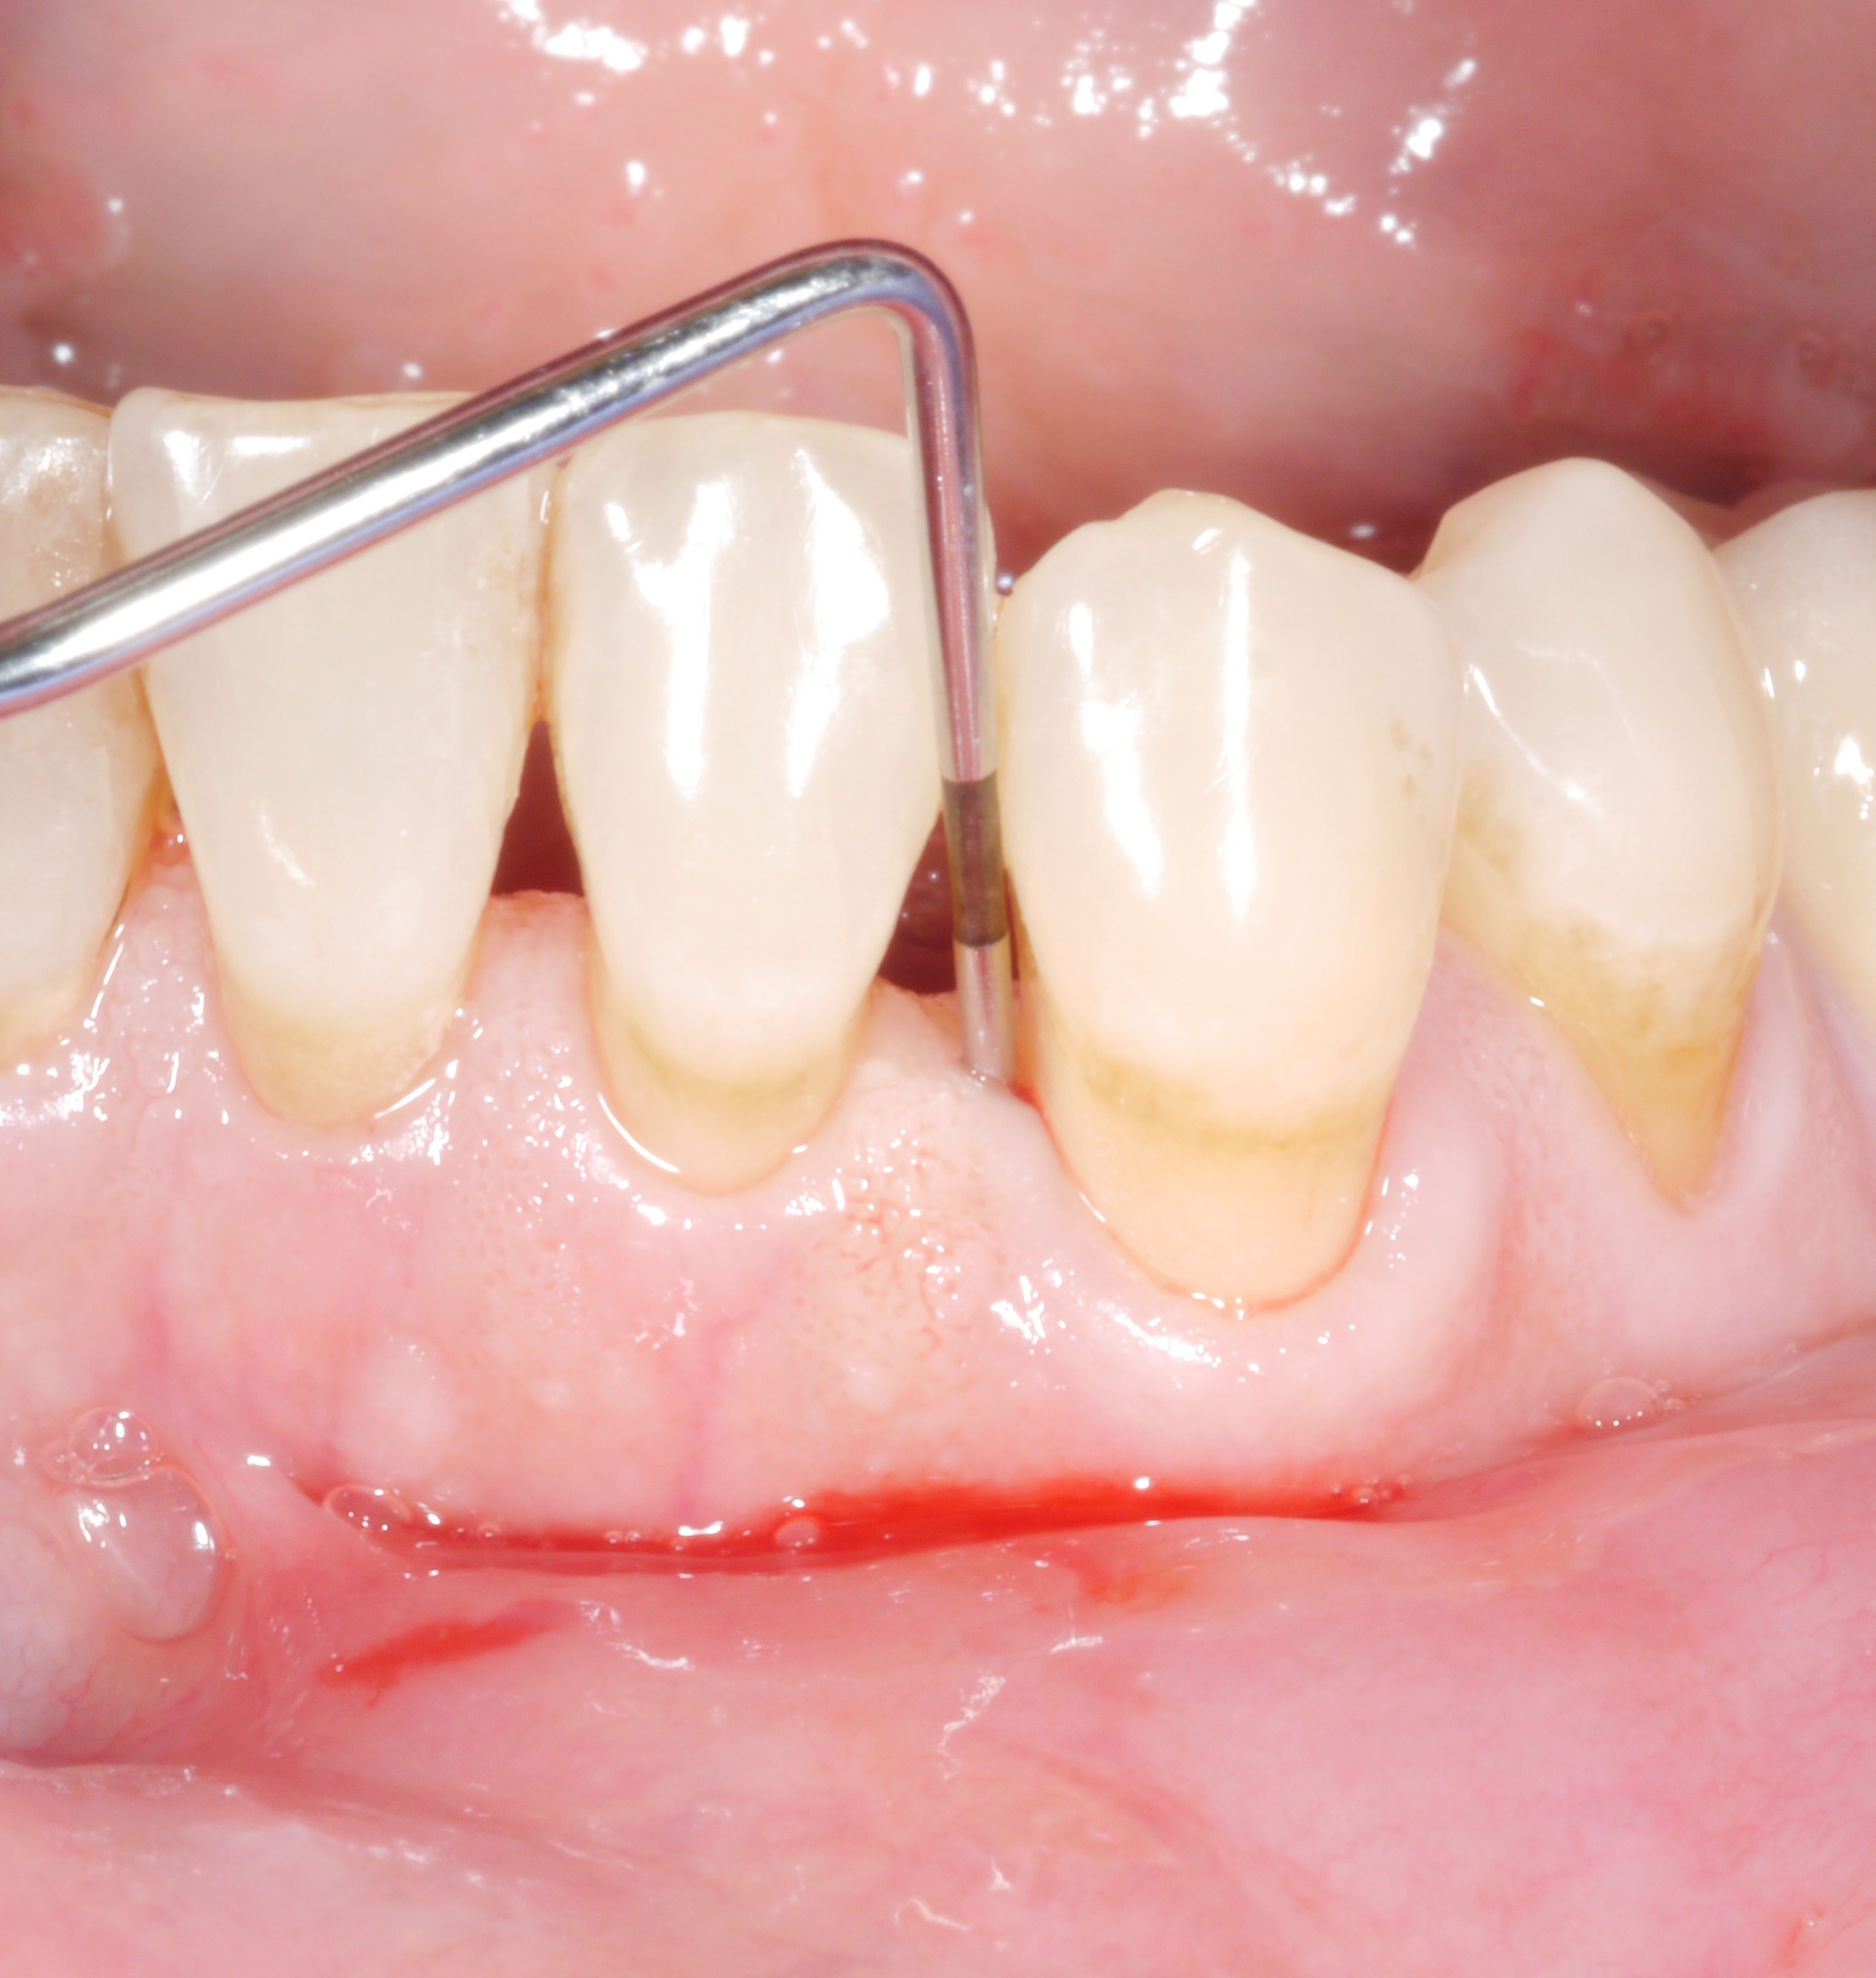

Man kennt die Situation nur allzu gut: Nach der aktiven Therapiephase weisen fast alle Zähne keine erhöhten Sondierungstiefen mehr auf, aber da sind noch diese 1 bis 2 Stellen, wo man das Therapieziel leider nicht erreichen konnte. Da liegt der Gedanke nahe: „Wie schlimm kann das schon sein? Eine einzelne Tasche mit 6 oder 7 mm – das kann doch keinen wesentlichen Unterschied machen …?“

Man sollte sich jedoch bei verbliebenen Sondierungstiefen nicht zu schnell zufrieden geben, denn bereits einzelne Restsondierungstiefen von mehr als 4 mm stellen zumindest auf längere Sicht gesehen ein Problem dar – sowohl für den betroffenen Zahn als auch für die Restbezahnung!

Fazit: Das Therapieziel sollte maximal 4 mm Sondierungstiefe und Entzündungsfreiheit sein!